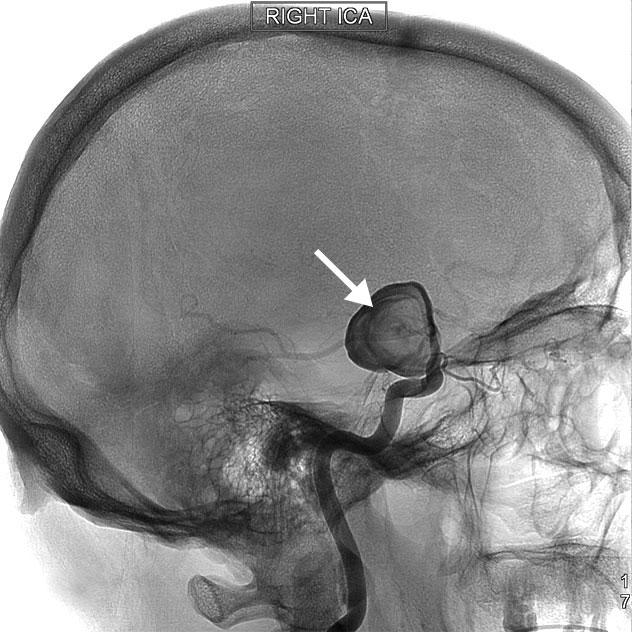

Cerebral angiogram

A cerebral angiogram showing a carotid aneurysm associated with stroke

• Cerebral angiogram. This test is less common, but it provides a detailed view of arteries in the brain and neck. A thin, flexible tube called a catheter is inserted through a small incision, usually in the groin. The tube is guided through the major arteries and into the carotid or vertebral artery in the neck. Then a dye is injected into the blood vessels to make the arteries visible under X-ray imaging.